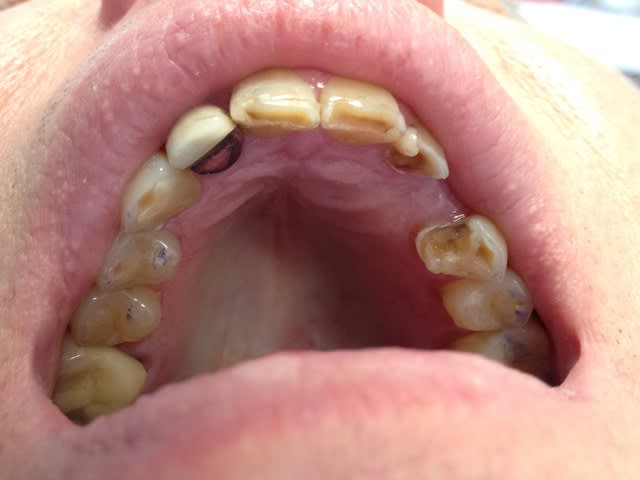

Ce monsieur que j'ai vu pour la première fois la semaine dernière vient pour remplacer la 23, il a eu précédemment un bridge collé qui lui a donné satisfaction pendant 15 ans. Il est tombé une fois il y a quelques années.

il aimerait améliorer l'esthétique des dents antérieures.

il ne se rend pas compte de son bruxisme et pense que les usures de ses dents sont liées au bridge collé.

ma question : que feriez vous ?

Bridge collé, bridge conventionnel, autre ? dévitalisation des piliers ou pas ?

Je vois bien qu'il y a des images sous 16 et racine M de 36, mais 12 ?